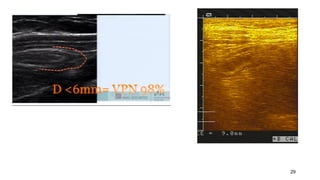

APPENDICITE

– Appendice de D> 6mm

Appendicitis : US